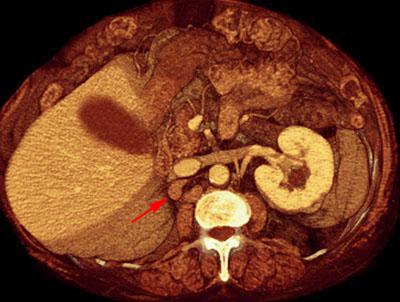

Recidiva adenopática de hipernefroma

VR seccional. Visión axial caudal. TC contrastado en fase venosa como control de nefrectomía derecha mostrando recidiva adenopática a nivel retrocava (flecha)